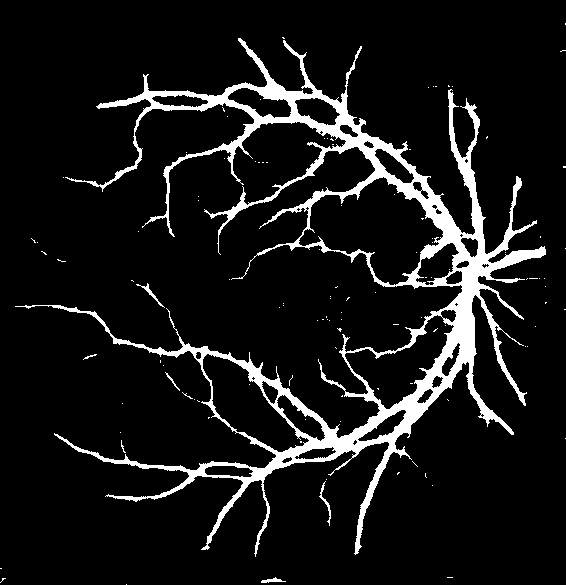

Refer to caption

(a) Original image

(b) Ground truth

(c) Level-I balancing

(d) Level-II balancing

(e) Original image

(f) Ground truth

(g) Level-I balancing

(h) Level-II balancing

Figure 6: Visual results after level-II balancing.

Impact of Level-II Balancing: This section analyzes the impact of applying Level-II balancing on top of Level-I balancing to the same sample images as in the previous sub-section. Specifically, the outcomes of applying Level-I and Level-II balancing are compared and graphically demonstrated in Figure 6. The application of Level-II balancing results in a significant performance boost over Level-I balancing, as indicated by higher values of all performance measures. Similarly, Figure 6 shows the visual outcomes of Level-II balancing for the sample DRIVE images along with their ground truths. The output segmentation masks show the detection of thin retinal blood vessels much closer to the ground truth binary mask than the images for Level-I balancing. The red rectangle is highlighted as a focus area for conveniently comparing the results. It can be concluded from comparing the results that Level-II balancing detects most of the vessel’s pixels, especially thin vessels, thereby significantly improving the sensitivity.